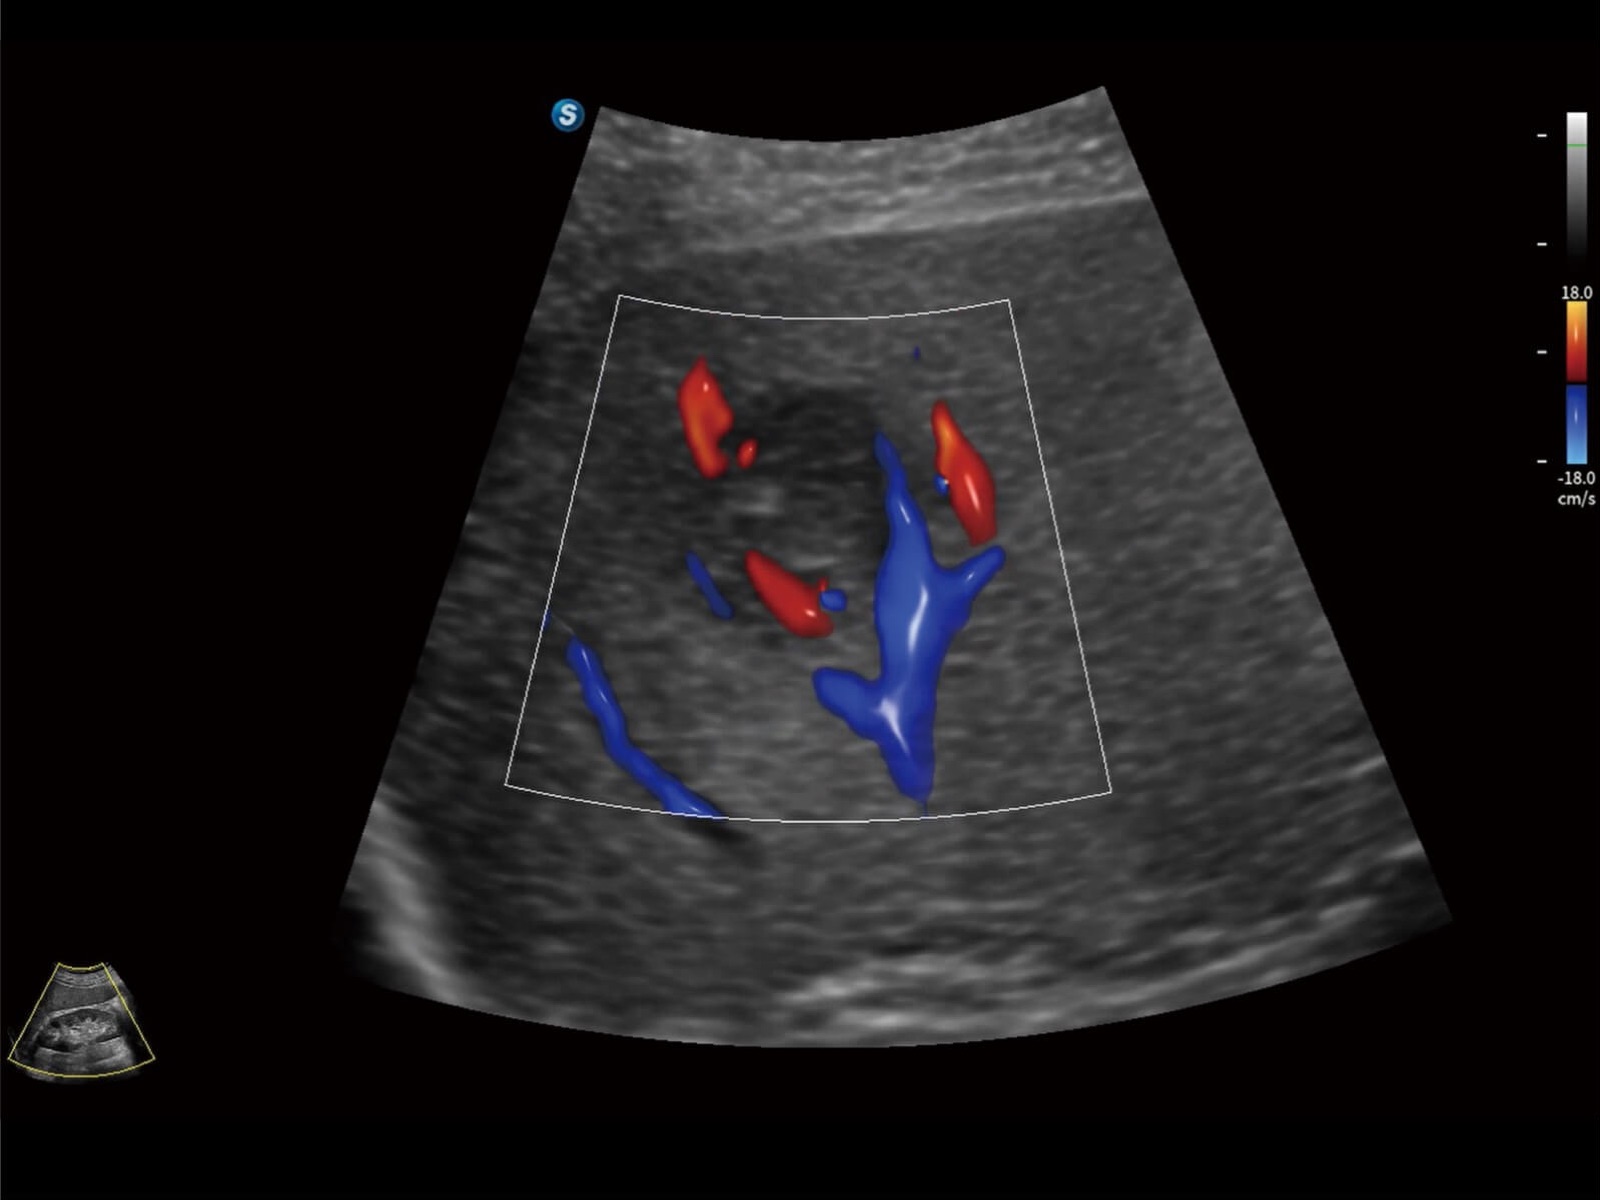

Bright Flow立体血流成像

通过光照模型,使二维血流显示出立体的效果,增加血流的敏感性、成束性,减少外溢。可以和其他不同的血流技术联合使用,轻松应对微小血管,增强血流的立体效果,提升视觉敏感性。